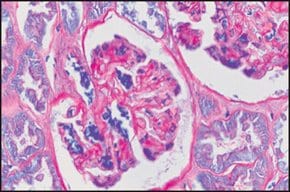

Periodic Acid-Schiff (PAS) Staining System,